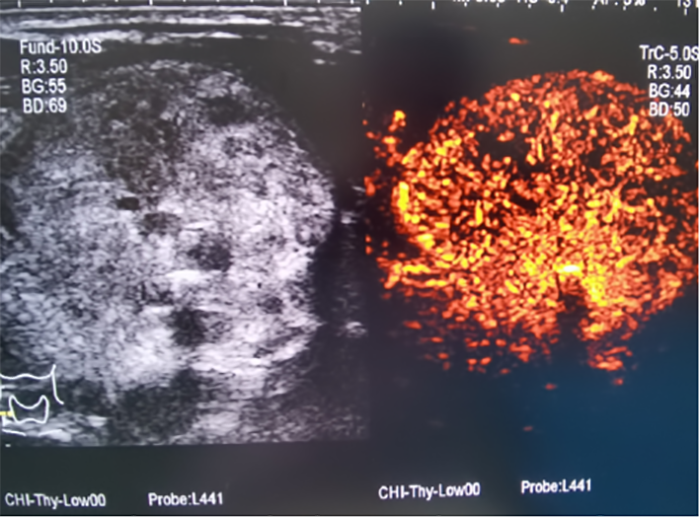

▲消融前,超声造影提示甲状腺结节内部血供丰富,活性大。